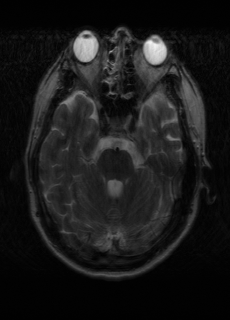

As we observe from the right image in Fig. 2, our BRM, both from MIMO and SISO settings, predicts the performance of dedicated models with a high correlation. We further choose the best three , and perform the last stage of fine-tuning accordingly to (6). A visual evaluation on real data is shown in Fig. 3. For simulated data, please refer to the Supplemental Material section.

Base on the best performing , we perceive that among , , and FLAIR, the results are best when is sampled the most. We suggest that this makes intuitive sense as images provide the best contrast out of the three sequences, which can compensate for the details lost in other images. The same observation can be made on the simulated data, where both and FLAIR show good contrast. When the time setting is changed to non-uniformity, we can see that our search for the best sampling strategy reflects the change. is sampled more as a result of faster acquisition time, while is still sufficiently sampled.

| Sequence | LR | SISO | MIMO | MIMO tuned | GT |

|---|---|---|---|---|---|

(a) 34.38/0.9371

(a) 34.38/0.9371

|

(b) 42.42/0.9883

(b) 42.42/0.9883

|

(c) 44.60/0.9920

(c) 44.60/0.9920

|

(d) 45.50/0.9940

(d) 45.50/0.9940

|

(e) PSNR/SSIM

(e) PSNR/SSIM

|

|

(f) 29.74/0.8903

(f) 29.74/0.8903

|

(g) 36.25/0.9734

(g) 36.25/0.9734

|

(h) 36.42/0.9752

(h) 36.42/0.9752

|

(i) 37.70/0.9832

(i) 37.70/0.9832

|

(j) PSNR/SSIM

(j) PSNR/SSIM

|

|

(k) 39.89/0.9311

(k) 39.89/0.9311

|

(l) 43.94/0.9864

(l) 43.94/0.9864

|

(m) 44.74/0.9883

(m) 44.74/0.9883

|

(n) 45.49/0.9894

(n) 45.49/0.9894

|

(o) PSNR/SSIM

(o) PSNR/SSIM

|